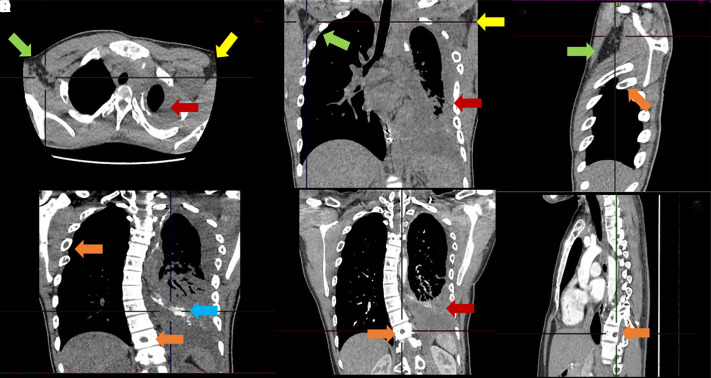

Case presentation: We present a case of a 19-year-old male with Gorham-Stout disease, multiple cervical lymphangiomas, and several thoracic complications successfully treated with sirolimus.

Abstract Image